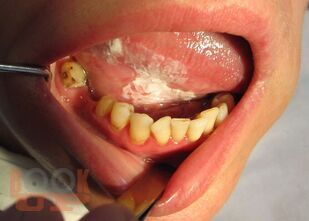

Злокачественные новообразования и восстановительная хирургия челюстно-лицевой области

Приведены материалы по общим и частным вопросам онкостоматологии и восстановительной хирургии челюстно-лицевой области. Изложены принципы обследования и современные методы лечения больных с онкопатологией челюстно-лицевой области, в соответствии с общепринятой классификацией описывается клиника отдельных нозологических форм заболеваний.

Описаны показания и противопоказания к восстановительным и реконструктивным операциям челюстно-лицевой области, принципы их планирования.